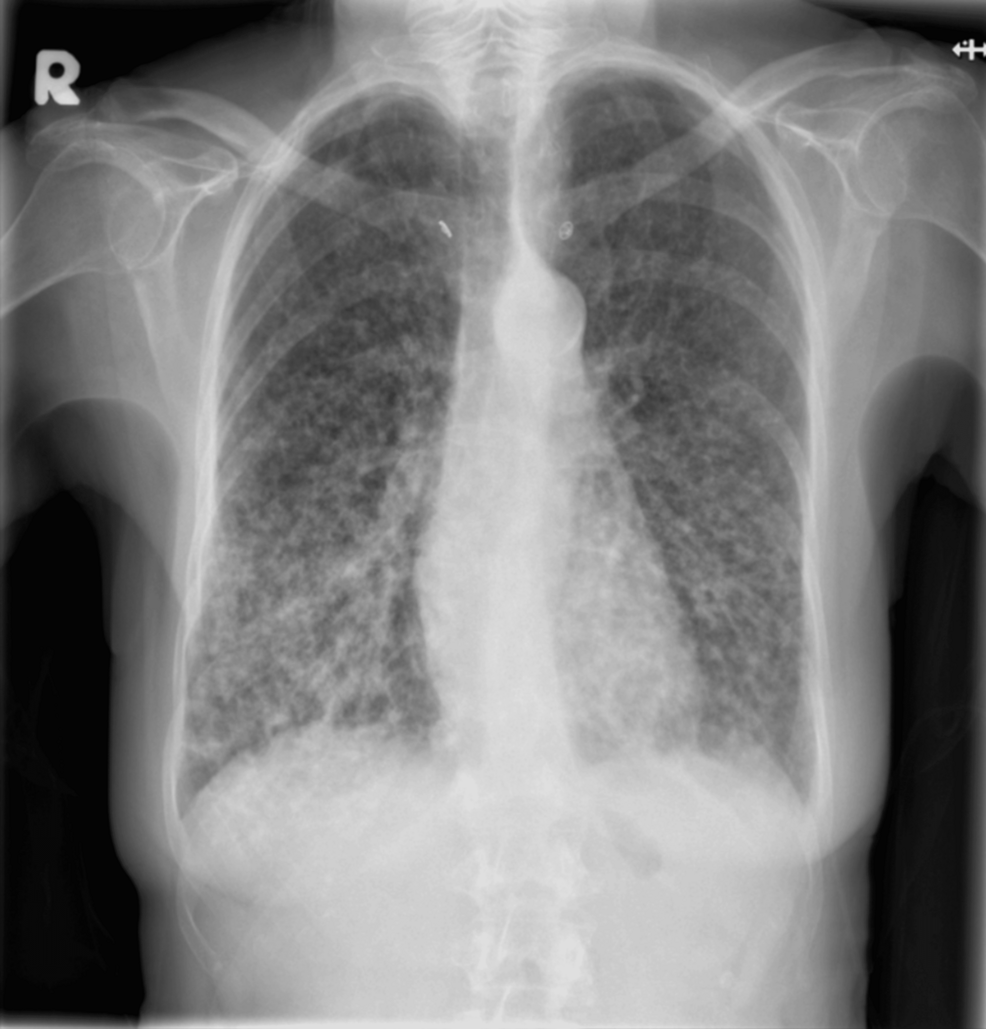

影像学检查:复查胸片示双肺弥漫性斑片状浸润影较前进展,以中下部肺野为主,背景伴多发结节影(图3)。

图 3 就诊后两个月胸部 X 线检查